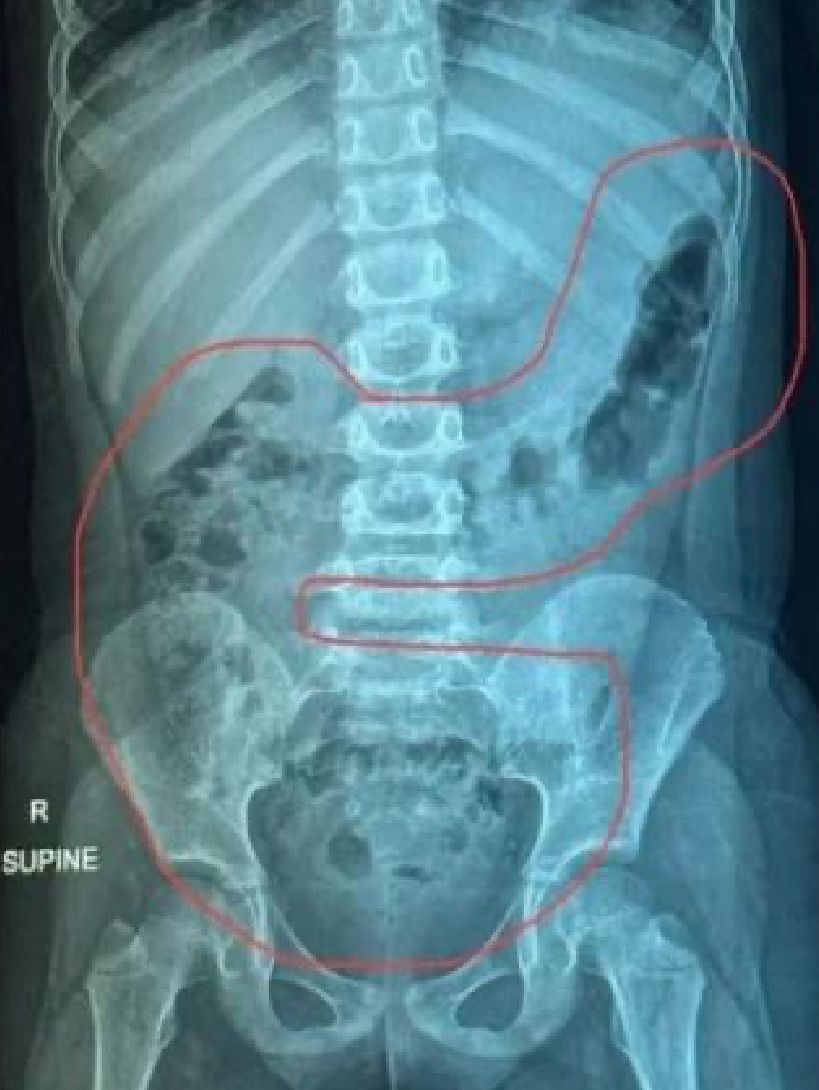

便秘問題|你有便秘問題嗎?一名5歲女童早前因常常肚痛去求醫,一開始被診為腸胃炎。但她食藥後情況並沒有改善,每天腹痛最少3次,再次去求醫進行X光檢查,才發現女童的腹部宿便已壓迫到肺部!

因為情況持續了2星期,醫生最後轉介了女童去進行X光檢查,一照之下,發現女童宿便量很多,已壓迫到肺部,所以造成腹痛。幸好,經過醫生的三日治療後,女童的大便被軟化,最後排出數公斤大便!原來是因為女童長期抗拒吃蔬菜,家長又以為可以用生果代替,最後導致嚴重便祕。